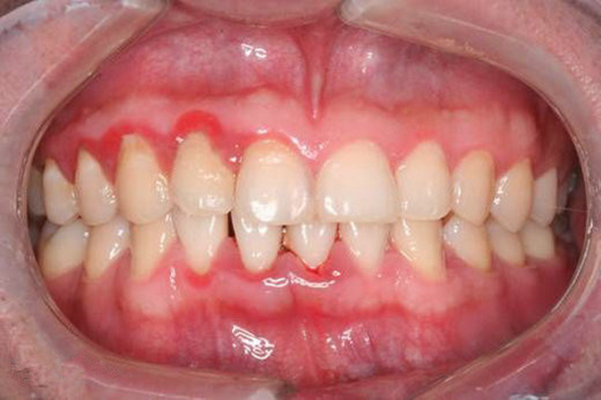

牙周炎圖片

牙周袋 (7)